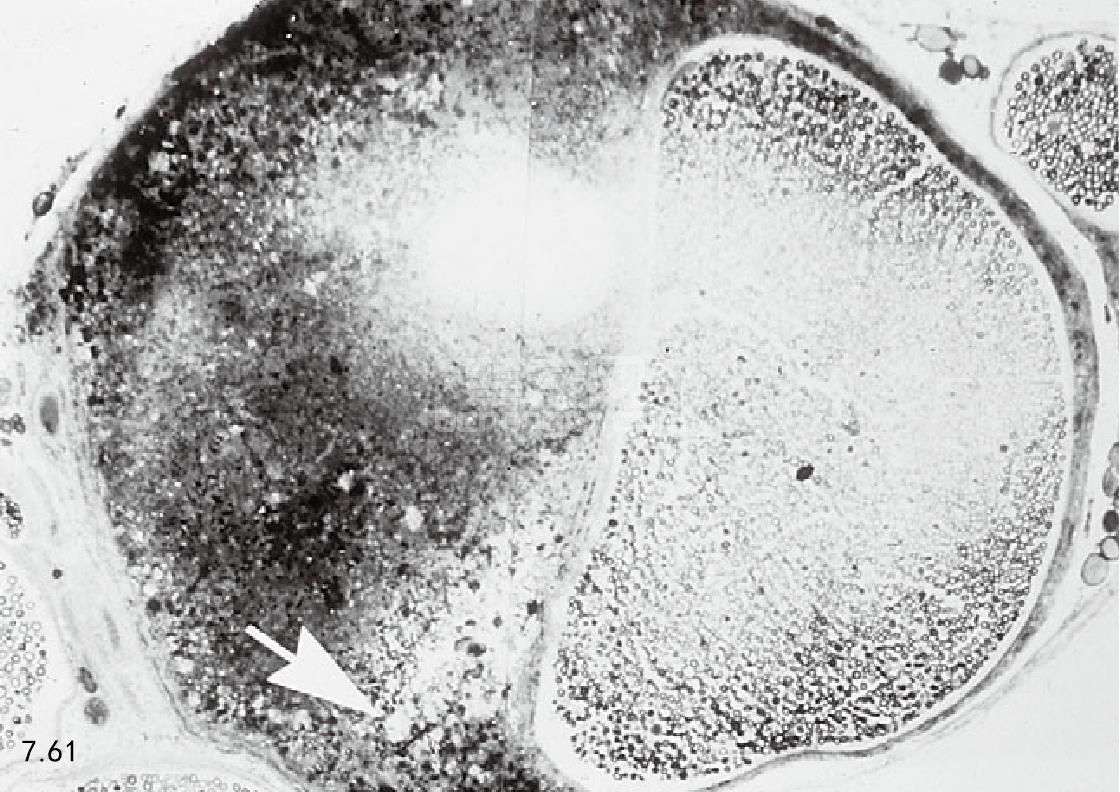

病理生理学 单肢轻瘫,霍纳氏综合征,面肌和咀嚼肌麻痹见于猫的脂蛋白脂酶缺乏和高乳糜微粒血症(图 7.60)。当神经穿过椎间孔或经过骨骼突起时,脂质颗粒压迫外周神经引起单肢轻瘫(图7.61)。

图7.61 患高乳糜微粒血症猫的神经束受压迫(箭头所指)。